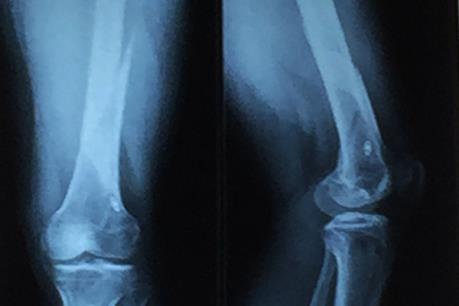

Sau khi thăm khám và chụp CT – scan, các bác sĩ Khoa Tiết niệu Bệnh viện Đại học Y Dược Thành phố Hồ Chí Minh phát hiện người bệnh bị sỏi san hô kích thước 74mm x 48mm, chiếm hết toàn bộ thận và các đài thận.

Đây là trường hợp sỏi thận phức tạp, hiếm gặp. Tên gọi sỏi san hô là do viên sỏi lấp đầy toàn bộ các nhánh đài thận, nhìn như một tảng san hô dưới biển. Nếu không điều trị sỏi sẽ tàn phá làm mất chức năng thận. Không những thế, sỏi còn có thể gây ra những đợt nhiễm trùng thận tái đi tái lại, đôi khi nhiễm trùng nặng có thể gây nguy hiểm tính mạng.

Áp dụng thành công phương pháp phẫu thuật nội soi lấy sỏi thận qua da. Ảnh minh họa: Thanh Thương – TTXVN